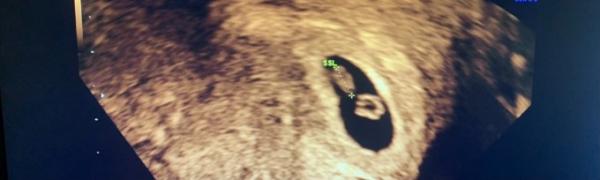

Hallo tolle Fotos ich hab auch am 20.06. ET mein letztes Bild ist von Dienstag da war ich 7+2 !

Bild zu